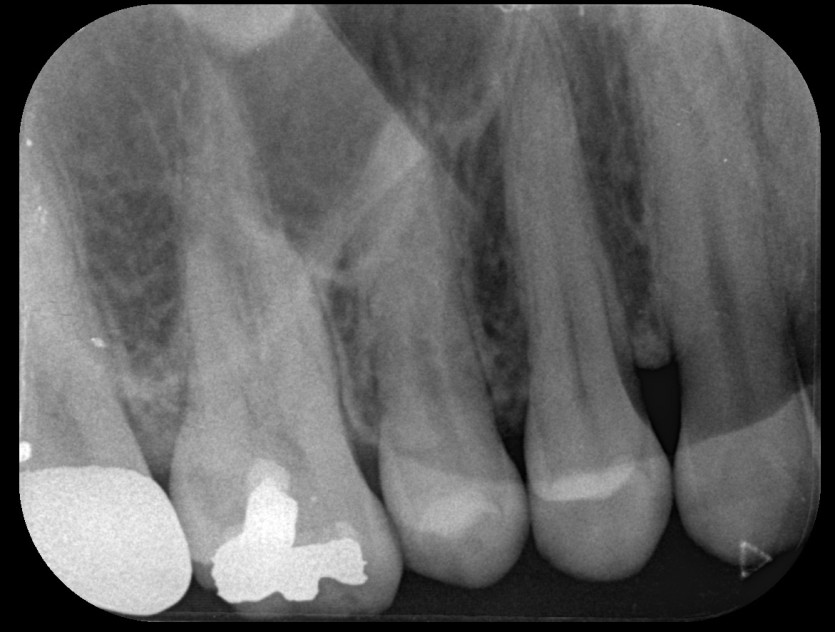

임플란트 사례